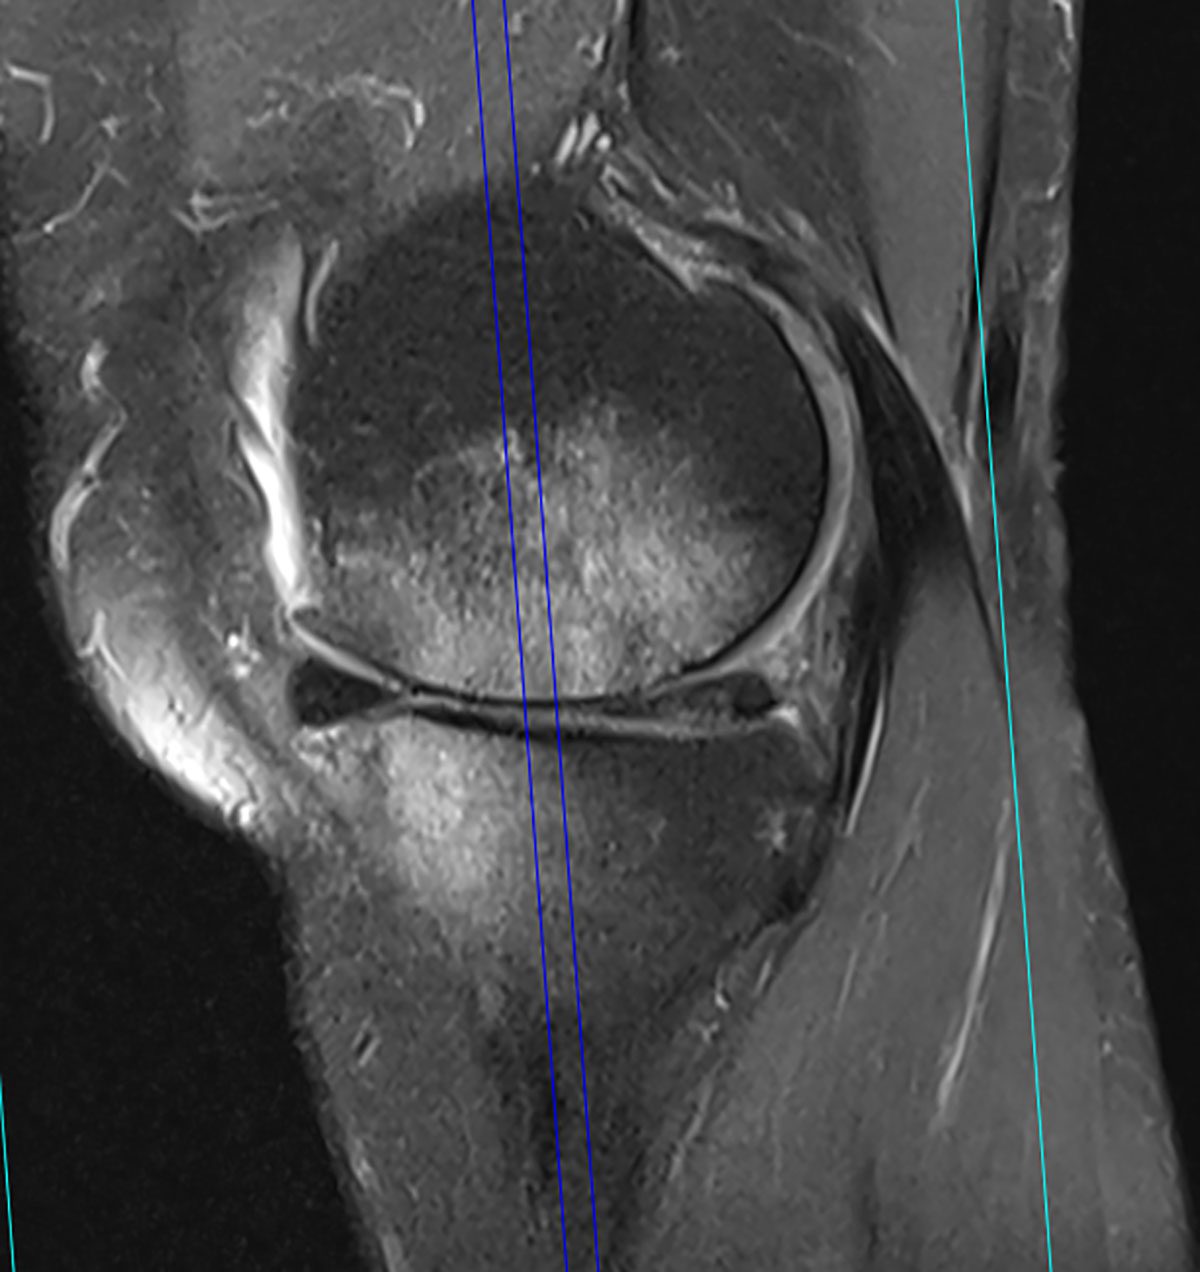

Es handelt sich bei der Patientin um eine uns bereits bekannte 64-jährige, aktive Patientin, die wir zuletzt im Frühjahr 2020 in unserer Praxis behandelt hatten. Die Patientin hat eine im Rahmen eines M. Ahlbäck vor einigen Jahren entwickelte, ausgeprägte Varusgonarthrose mit seinerzeit erheblichem Knochenödem (Abb. 2). Sie berichtete, dass sie seit unserer letzten Behandlung nahezu zwei Jahre weitestgehend beschwerdefrei gewesen sei und ihren Alltag einschließlich moderater sportlicher Aktivitäten gut bewältigen konnte. Nun musste sie sich im Rahmen der Haushaltsauflösung ihrer hochbetagten Mutter einer hohen körperlichen Belastung aussetzen, wodurch die Beschwerden wieder reaktiviert wurden. Ein aktuelles Kontroll-MRT hatte sie bereits durchführen lassen und bat um den schnellen Beginn einer neuen Behandlungsserie.

Das kürzlich durchgeführte MRT des rechten Kniegelenkes (06/2022) zeigt eine deutlich aktivierte Varusgonarthrose, aktuell wieder mit einer Zunahme des Knochenödems im Vergleich zu deren Voraufnahmen, einen Reizerguss sowie eine kleine Bakerzyste.